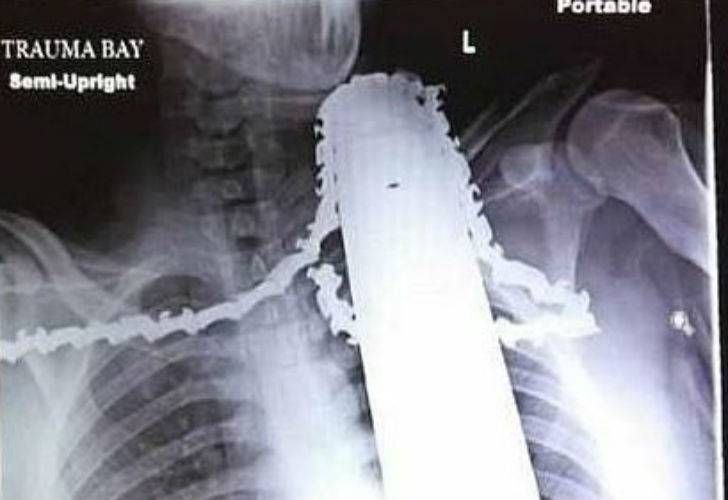

Una motosierra le perforó el cuello y sobrevivió

La filosa hoja quedó a un centímetro de la arteria carótida. Está estable.

En medio de la desgracia, la suerte le hizo un guiño y le regaló un renacer a James Valentine, quien estuvo a punto de perder la vida cuando la motosierra que manipulaba se le clavó hasta el cuello. Con la radiografía como testimonio del milagro, el afortunado aún no puede creer que la filosa hoja se haya detenido a solo un centímetro de la arteria carótida.

Este trabajador de 21 años estaba podando un pino en la ciudad de Ross Township, Estados Unidos, cuando perdió el control de la motosierra y se la clavó en el pecho deslizándose peligrosamente hasta su cuello.

Sus compañeros de una empresa de mantenimiento de árboles en Pittsburgh reaccionaron rápidamente desactivando el aparato, pero le dejaron la hoja en el cuerpo y así lo llevaron al hospital.

Los médicos quedaron estupefactos puesto que la motosierra no dañó la médula espinal, el esófago ni las vías respiratorias. Sólo afectó músculos y tejido el hombro.